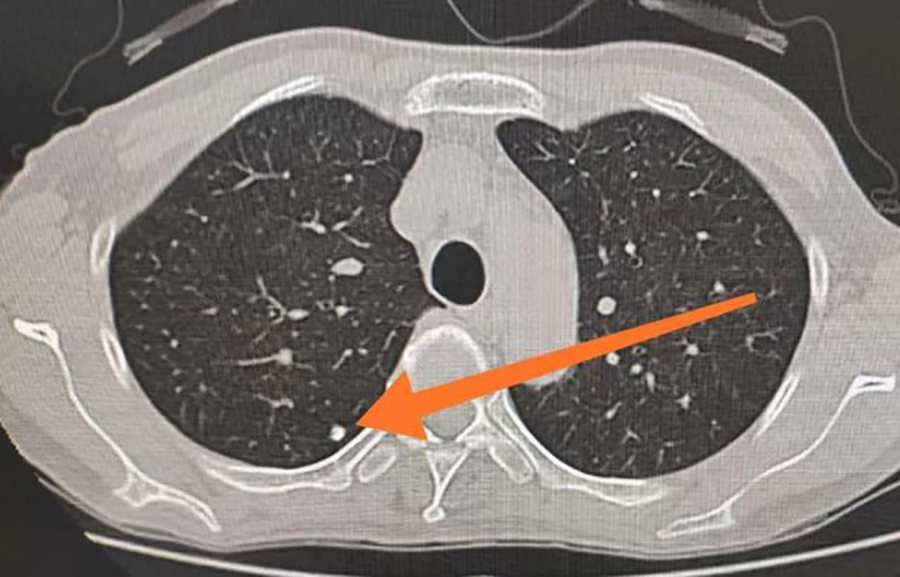

肺结节意味着得了肺癌吗?要做手术吗?同样的问题也困扰着40岁出头的李先生。一次体检中,李先生被查出双肺肺实性结节,最大的约6mm,这着实把他吓了一跳。因为不了解肺结节,让他产生了紧张、恐慌、焦虑情绪。于是,他便来到了中文成人网 平阳部肺病科就医。平阳部肺病科副主任王丽娜说,肺结节是影像学表现为直径≤3cm大小,局灶性、类圆形、密度高的阴影,通常不会引起临床症状,起病隐匿、不易发现,是近年来的常见病。其中,直径≤1cm时通常被描述为小结节,而直径≤0.5cm时被称为微小结节。除了大小以外,还根据结节的密度不同分为纯磨玻璃结节、部分实性磨玻璃结节和纯实性结节。

王丽娜说,临床上初次发现的肺部结节多数为良性病变。良性结节大多数是肺结核或者肺部炎症,经过治疗之后,局部组织形成瘢痕性的修复,从而表现为结节。但是,其中仍有一定比例为恶性肿瘤早期表现,比如伴有分叶、毛刺、胸膜凹陷征、支气管截断征、支气管充气征、血管集束征等变现,则考虑恶性病变的可能性较大。所以,在确诊为肺部结节后,大家也无需过度恐慌,一定要遵医嘱定期复查肺CT,以明确结节有无增长以及形态变化等问题。